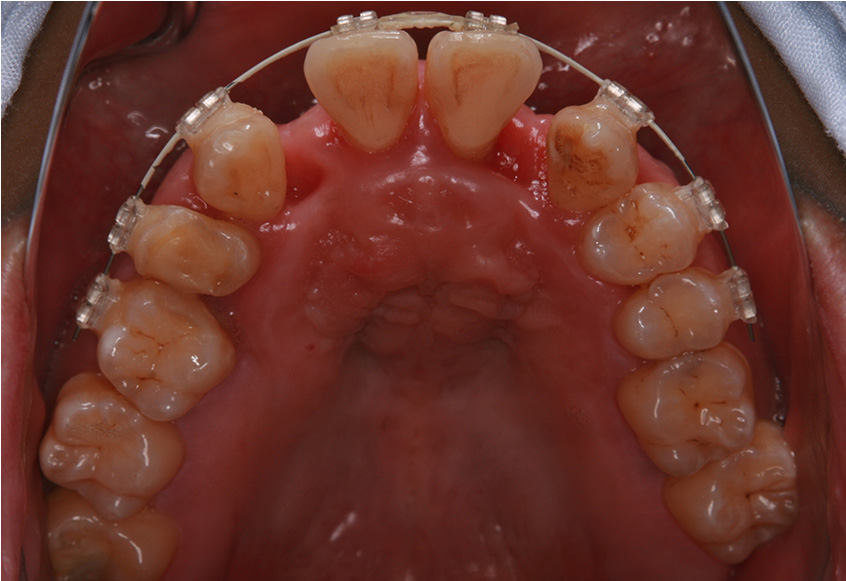

治療開始後3ヵ月経過すると、前歯の隙間や全体の乱れが減ってきました。口笛が吹けるようになったとのことです。

最初のお口の中 治療開始3ヵ月後